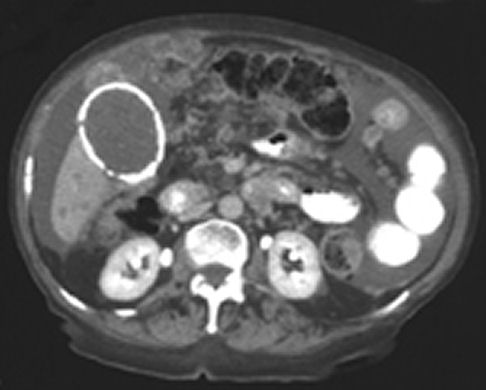

A computed tomographic scan showed that the calcification seen on the plain abdominal radiograph represented the wall of

the gallbladder (image below). The scan also showed ascites, multiple lesions in the liver, and nodularity of the

peritoneum and small bowel mesentery. These findings suggested metastatic carcinoma of the gallbladder, but the patient

refused further investigation.

Calcification of the gallbladder wall—referred to as “porcelain gallbladder”— is a rare form of chronic cholecystitis

affecting women predominantly. It should always be considered in the differential diagnosis of a calcified lesion in the

right upper abdominal quadrant. Confirmation of porcelain gallbladder can be achieved by ultrasonography or computed

tomography. Because patients with a calcified gallbladder have an increased risk of gallbladder cancer, cholecystectomy

is indicated in most cases.